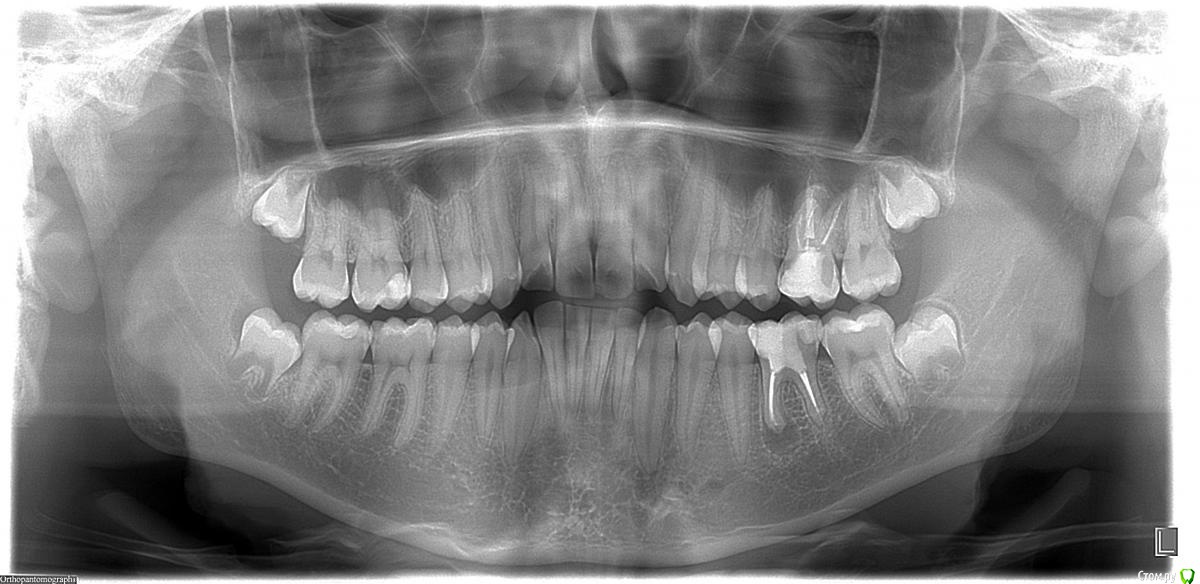

igorstom Опубликовано 10 декабря, 2016 Автор Поделиться Опубликовано 10 декабря, 2016 2014 год. Ну ведь явная же гранулема (кисто-гранулема)? Зуб 3.6 Ссылка на комментарий

igorstom Опубликовано 10 декабря, 2016 Автор Поделиться Опубликовано 10 декабря, 2016 В 2014 году у пациента были жалобы по поводу припухлости в области 3.6 зуба (делали периостотомию и назначили антибиотики - в поликлинике, и также настойчиво предлагали удалить), болезненность при накусывании в этот период. Попробовал всё перелечить. Ссылка на комментарий

igorstom Опубликовано 10 декабря, 2016 Автор Поделиться Опубликовано 10 декабря, 2016 И вот наконец заставил сделать контрольный снимок. К сожалению далеко не всех можно пронаблюдать пациентов. Хотя есть в планах создать тему "Отдаленные результаты". Есть пациенты, которые наблюдаются более 8 лет.Вопрос. Гранулема исчезла? Или снимок просто не показывает? Раньше зуб периодически при переохлаждении или простуде всегда давал знать. Сейчас более 1,5 лет ни разу не пискнул. Об эндо чуть позже напишу. Ссылка на комментарий